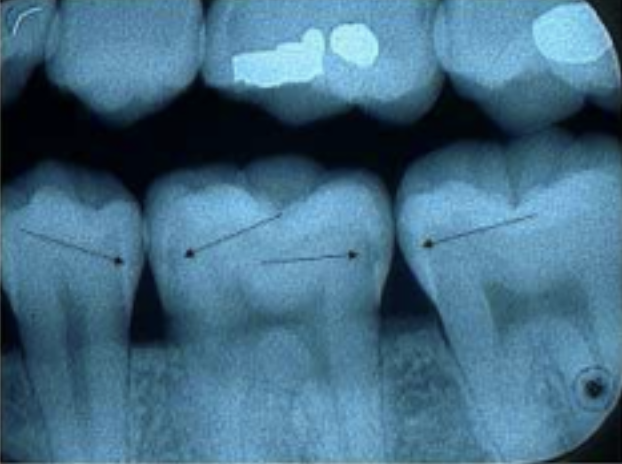

Figure 1: (Dorfman, n.d.). Radiographic imaging of tooth decay’s effect on enamel.

Figure 1:(n.d.). Radiographic tooth decay from Dental Education Information from Dr. Jeffrey Dorfman. Indicates what tooth decay looks like on enamel. [Review of Radiographic tooth decay from Dental Education Information from Dr. Jeffrey Dorfman. Indicates what tooth decay looks like on enamel. ]. Retrieved December 15, 2024, from